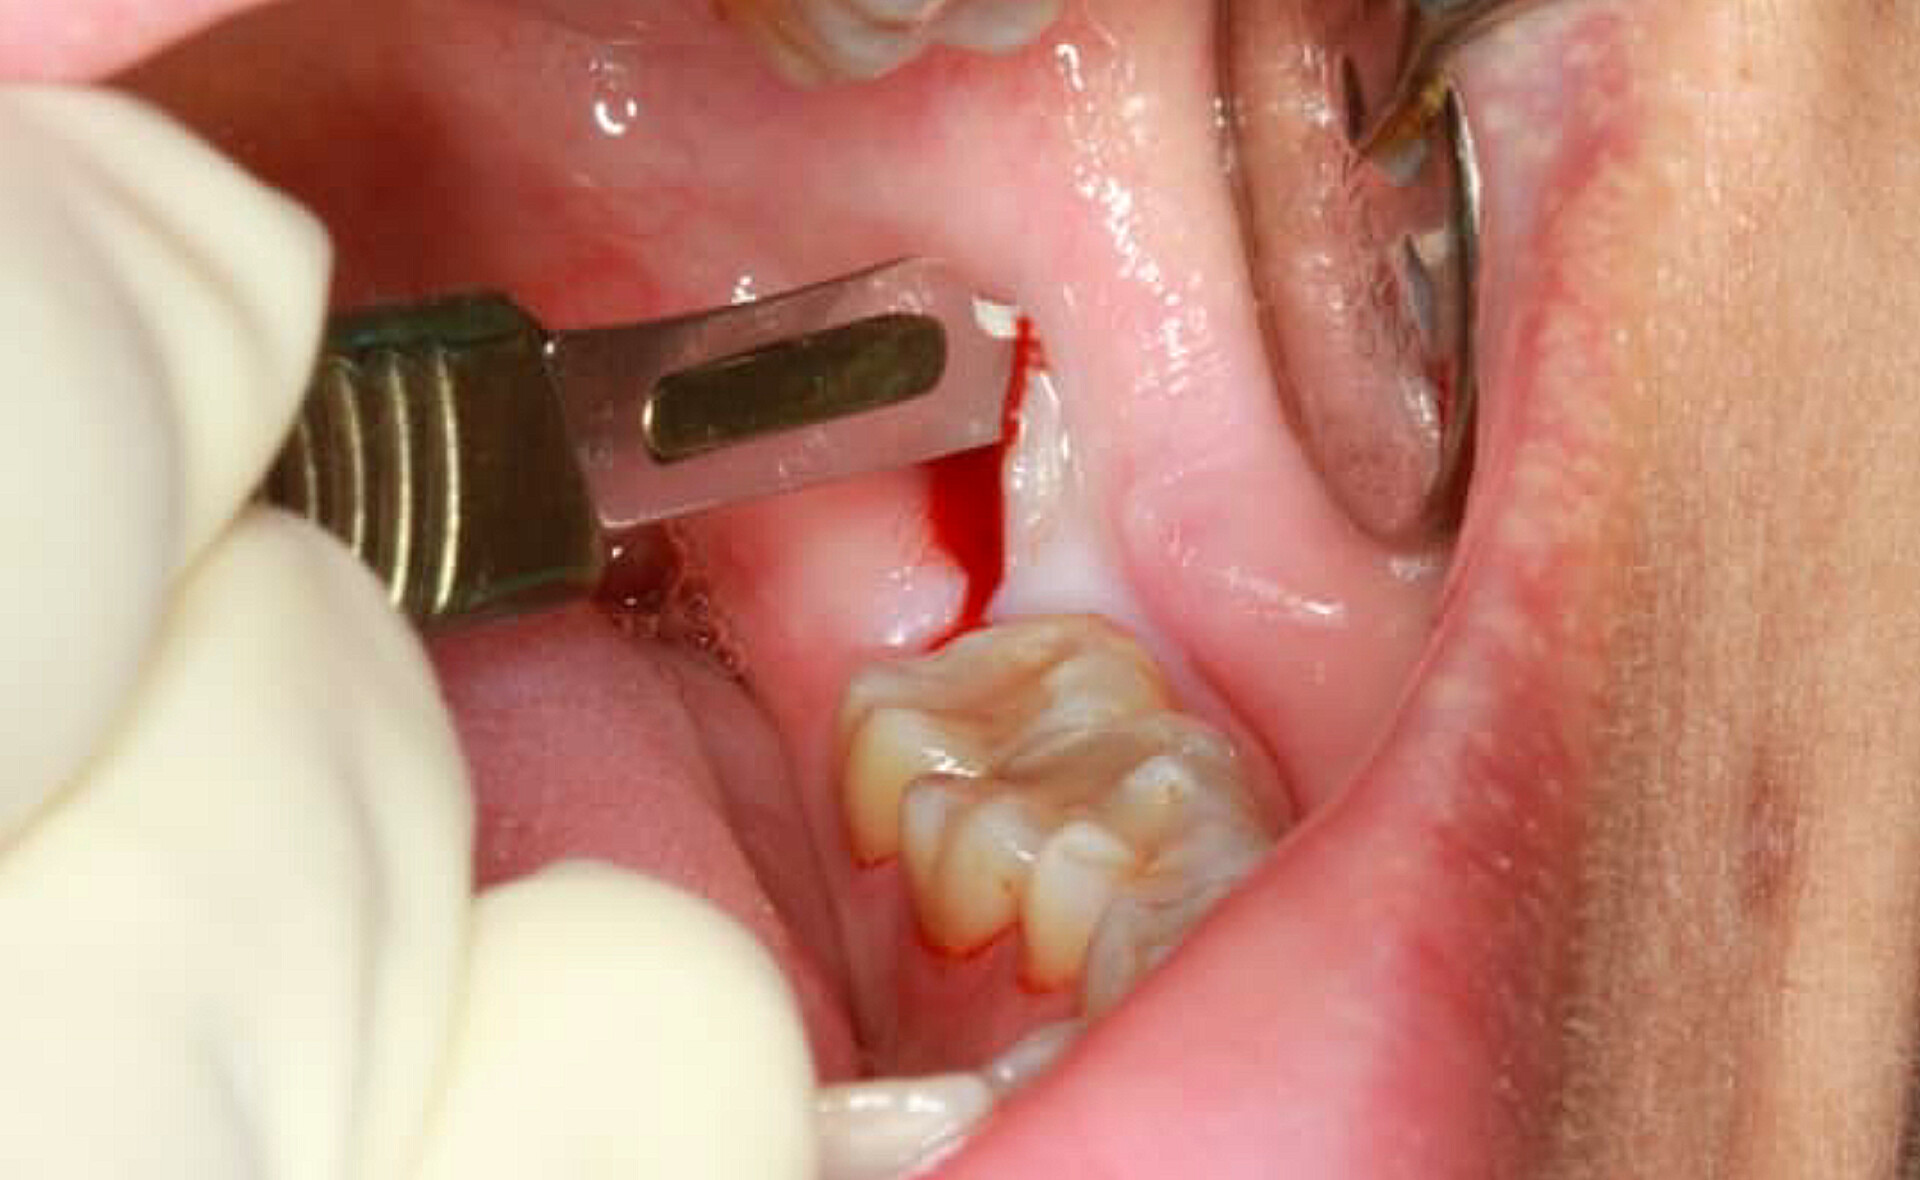

۷. جراحی دندان

کلیه خدمات جراحی دندان از جمله کشیدن دندان عقل، جراحی ایمپلنت و سایر اعمال جراحی دهان با بیحسی موضعی و در محیطی کاملاً استریل انجام میشود.